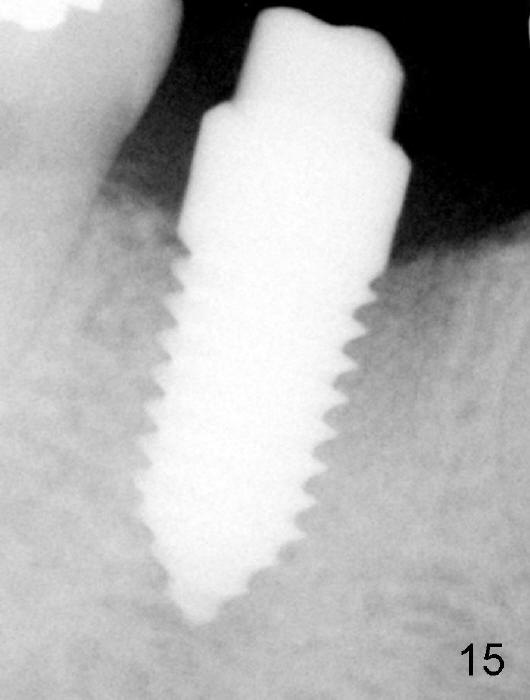

Fig.11: immediately post implantation (6x14 mm one piece). Fig.15: increased bone density in the mesial and distal sockets 3.5 months postop.